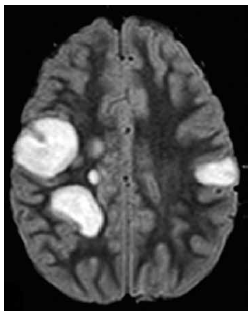

Menina de 9 anos de idade é levada ao pronto-socorro por sonolência e fraqueza muscular progressivas há 2 dias. Na avaliação, a criança se apresenta sonolenta, mas desperta aos estímulos vigorosos. Não responde aos comandos solicitados. Reflexos osteotendíneos são exaltados globalmente, e apresenta reflexo cutâneo plantar em extensão à esquerda e sem resposta à direita. O reflexo pupilar e o exame de fundo de olho são normais. Há 10 dias do início dos sintomas, ela apresentou quadro de infecção de vias aéreas superiores, a qual foi tratada com amoxicilina.

A imagem da ressonância magnética de crânio é mostrada a seguir.

O diagnóstico mais provável é